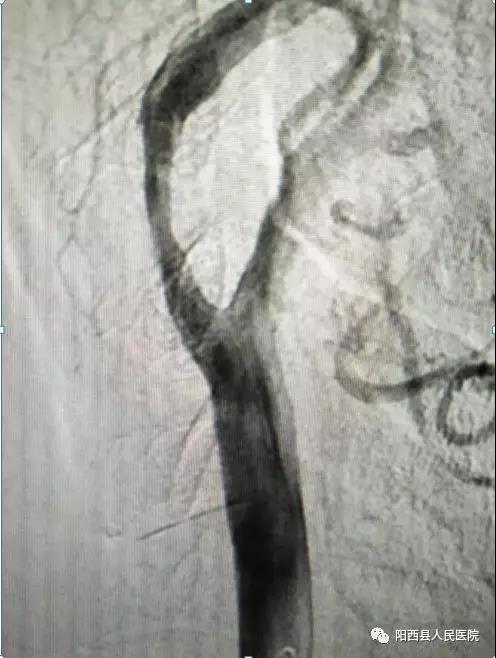

此次手术患者是一位84岁的老年男性,因左侧肢体乏力一天收住我院脑科中心。入院后完善各项常规检查,颅脑MRA示:右侧基底节区、放射冠脑埂塞。颈部血管彩超示:右侧颈内动脉起始段重度狭窄(狭窄》70%)。头颈部CTA示:右侧颈内动脉颈段混合性斑块,管腔中重度狭窄。排除禁忌后,进行DSA检查。术中发现RC1约60%症状性狭窄,在血管狭窄处放入支架1枚,患者血流情况恢复良好,左侧肢体肌力恢复,可自行行走。

DSA下支架植入影像